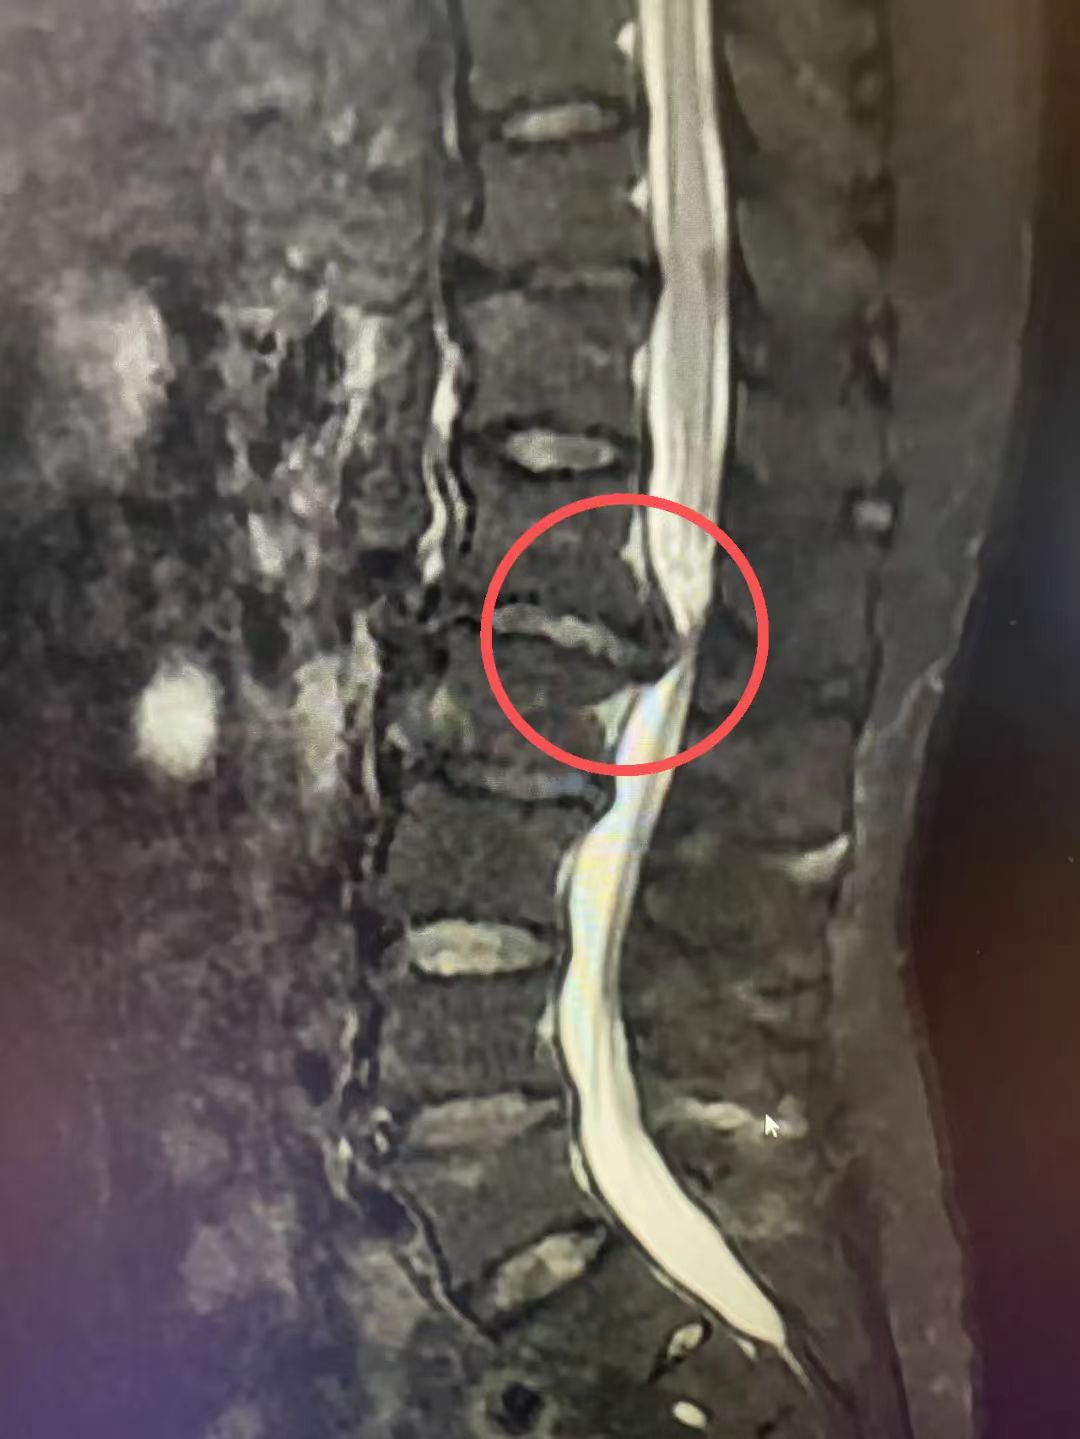

眼看生活受到严重影响,家人赶紧陪刘阿姨来到昆明同仁医院骨科就诊,经过详细的专科检查,医生发现刘阿姨的腰1—2椎间盘脱出,导致右侧神经根严重受压,这是一种相对少见的高位腰椎间盘突出症。与常见的腰4—5、腰5—骶1节段的突出不同,腰1—2节段位于胸腰交界区,解剖结构复杂,毗邻着控制下肢感觉与运动的脊髓圆锥,手术空间极为狭小。在此处进行操作,要求术者具备极其精细的解剖知识和稳定的手术技巧,任何微小的偏差都可能造成神经损伤等严重后果,导致患者下肢功能障碍甚至瘫痪。

考虑到刘阿姨腰痛伴右下肢放射痛明显,活动受限且行走困难,保守治疗已无法缓解症状,经过科室反复讨论,骨科专家团队决定迎难而上,为她实施“经后路L1/2椎板切除椎管减压神经根松解椎间盘摘除椎间植骨融合椎弓根钉棒系统内固定术”。

在麻醉科医护人员的护航下,贺刚副主任医师以“毫米级”的精准操作,小心翼翼地切除部分椎板,扩大狭窄的椎管,轻柔地将压迫神经根的脱出椎间盘组织完整摘除,彻底解除了对神经的压迫。随后,又成功实施了椎间植骨融合与内固定,如同为受损的脊柱段打上了坚实的“保险杠”,重建了脊柱的稳定性,经过数小时的努力,手术顺利完成。